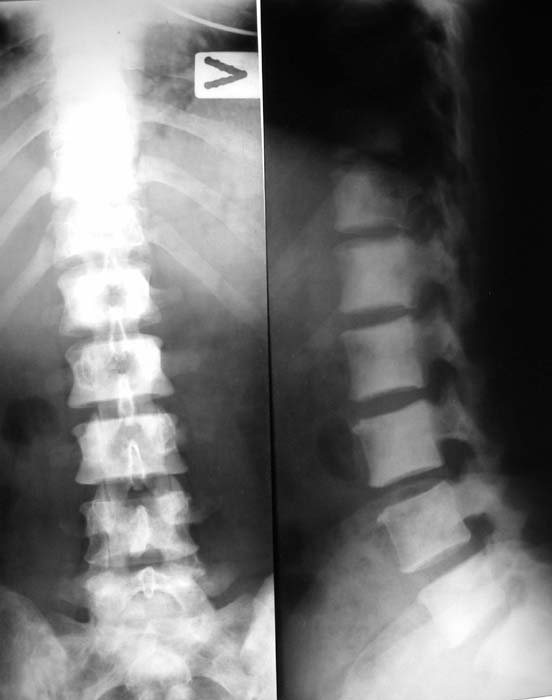

Женщина, 46 лет.

В течение четырех месяцев жалобы на боли в спине.

При МРТ (29.10.06) обнаружены диффузно-очаговые изменения в пояснично-крестцовом отделе позвоночника предположительно вторичного характера.

В октябре 2006 г. по поводу маточного кровотечения (менопауза 4 мес.) выполнено УЗИ - гиперплазия эндометрия, полипоз. Операция - удаление полипа, выскабливание полости матки. Цитологический анализ - пласты переходного климактерического эндометрия.Проведено комплексное исследование. В приложении: рентгенограммы и томограммы поясничного отдела позвоночника; радиологические исследованиямолочной железы, ЖКТ, почек, грудной клетки, анализы.УЗИ (18.12.06.) щитовидной железы, молочных желез - без патологии (умеренный фиброз по ходу млечных протоков).

Остеосцинтиграфия 4.12.06. - активный остеобластический процесс в поясничном, нижнегрудном отделах позвоночника, костях таза.Местными онкологами онко-процесс исключен. Фтизиатрический и онкогематологический диагнозы исключены.

Вопросы: 1. Диагноз? 2. Методы дополнительной диагностики? 3. Тактика лечения?